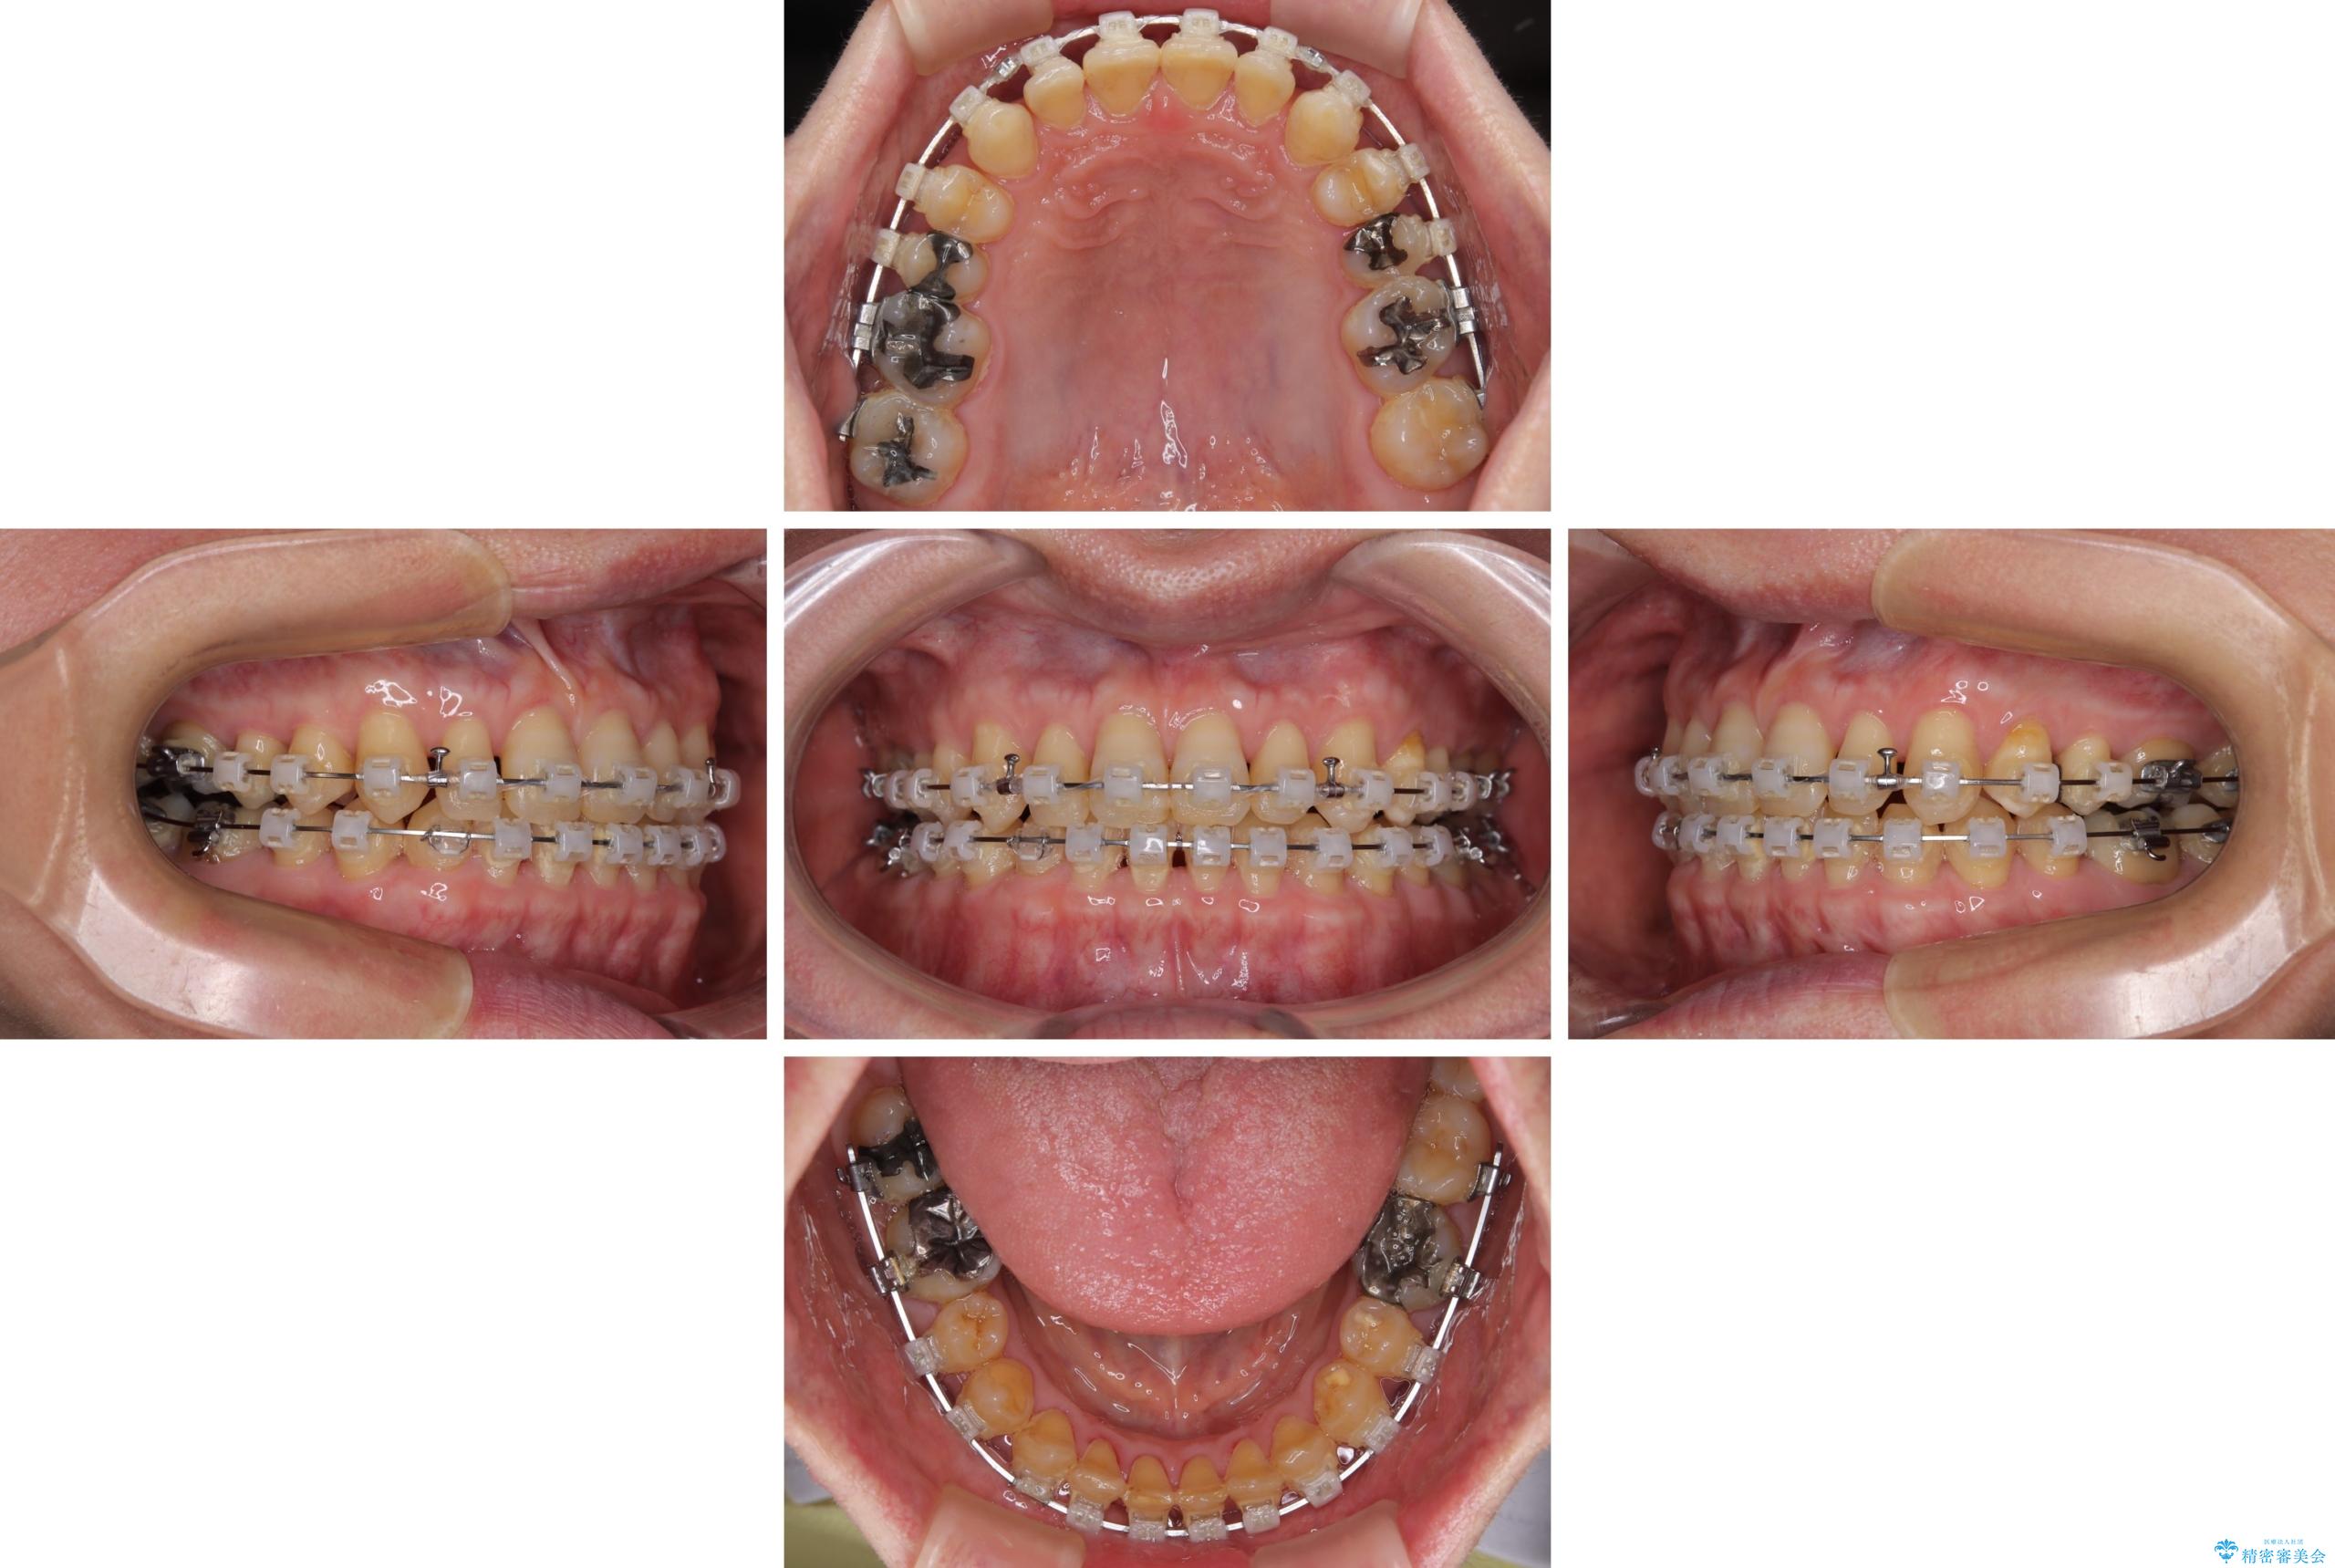

【モニター】ディープバイトで隙間の空いた歯列 ワイヤー装置での非抜歯矯正

- 前歯のデコボコと隙間の空いた歯列を気にして来院された患者様です。

下顎前歯が隠れるほどのディープバイトにより、強い咬合力と突き上げで上顎歯列に隙間が空いている状態でした。

手前に傾斜している奥歯をワイヤー装置で立ち上がらせ、咬み合わせの高さを挙上することで突き上げを解消し、空隙歯列を改善していくこととしました。